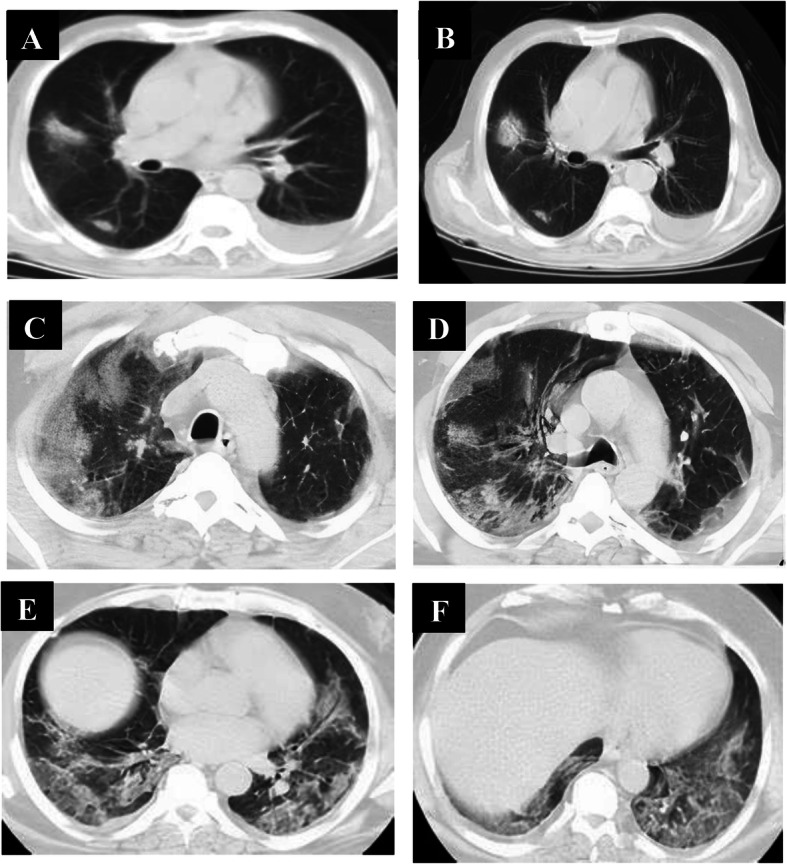

All patients in the late phase group (8–14 days, n = 36) had positive CT findings. CT abnormalities were combined GGO and consolidation in 36 patients, crazy-paving in 24 patients, reversed halo in 20 patients, and linear consolidation in 28 patients, and peripheral distribution of the pulmonary lesions was noted in 4 patients and diffuse distribution in 32 patients. All those patients had bilateral pulmonary affection: 4 lobes of affection in 13 patients and 5 lobes of affection in 24 patients. Total lung severity score: score 17 in 4 patients, score 18 in 12 patients, score 19 in 12 patients, and score 20 in 8 patients (Fig. 3).

Fig. 3.

A 45-year-old male patient complaining of cough, fatigue, and sore throat; no respiratory distress (mild symptoms). Non-contrast axial chest CT (a–d) 9 days from onset of symptoms (late phase) revealed multiple extensive confluent patchy areas of ground opacities and consolidation seen scattered at both lungs; central and peripheral in distribution